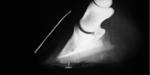

Morbid specimen showing total irreparable laminar damage

Venogram showing no blood supply to the dorsal laminae

The downward force of the bodyweight is neutralised by the resisting force of the ground. The primary forces involved are the pulling force of the deep digital flexor tendon, and the tearing force at the junction of the white line and the sole.

Biomechanical forces